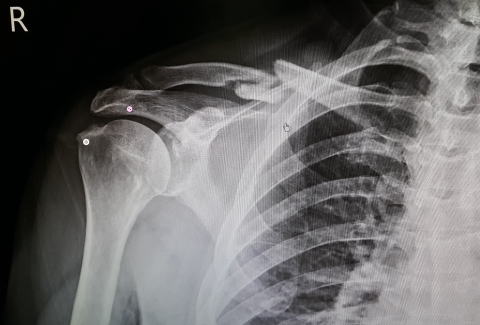

5ヶ月検診に行ってきました、肩を動かすと痛みが(-_-;)

と言うと。。

肩の骨2カ所(矢印部)に突起が出来ていて、それが筋と

当たり痛みの原因になっている、不可をかけた時の動き

でも可動部はちゃんと動いているで問題なし、消炎剤を飲

んで下さいと。。。

左側の丸印2点が突起と隆起、中央上部が骨折した箇所。。